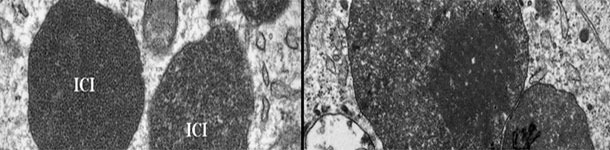

Microscopia elettronica di un linfonodo di un suino infetto da PCV2-SD. Notasi la presenza di corpi di inclusione intracitoplasmatici del PCV2 (ICI); in alcune zone le particelle virali possono presentarsi come strutture paracristalline (riquadro dell'immagine di destra). Foto cortesia di Carolina Rodríguez-Cariño, tesi di dottorato.